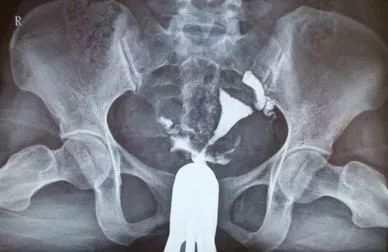

子宫输卵管造影是比较常用的一种检查手段,它的做法就是医生用一根专用的细管子,通过阴道将造影剂注入子宫输卵管,摄片后造影剂所到之处可以清楚的呈白色显影,因此可以从片子上观看子宫输卵管是否显影,对它的一些情况进行分析及诊断。

比如,有输卵管的病变、输卵管堵塞,通过子宫输卵管造影基本就可以看出来了。同时可以了解子宫、输卵管发育是否有畸形或者粘连等情况。.

子宫输卵管造影在不孕症诊疗中用的比较广泛,一方面它可以做出诊断,同时大部分不孕病人进行造影检查之后,因推送造影剂之后针筒需要加压,可能使轻度的输卵管粘连松解变通畅,达到治疗目的。